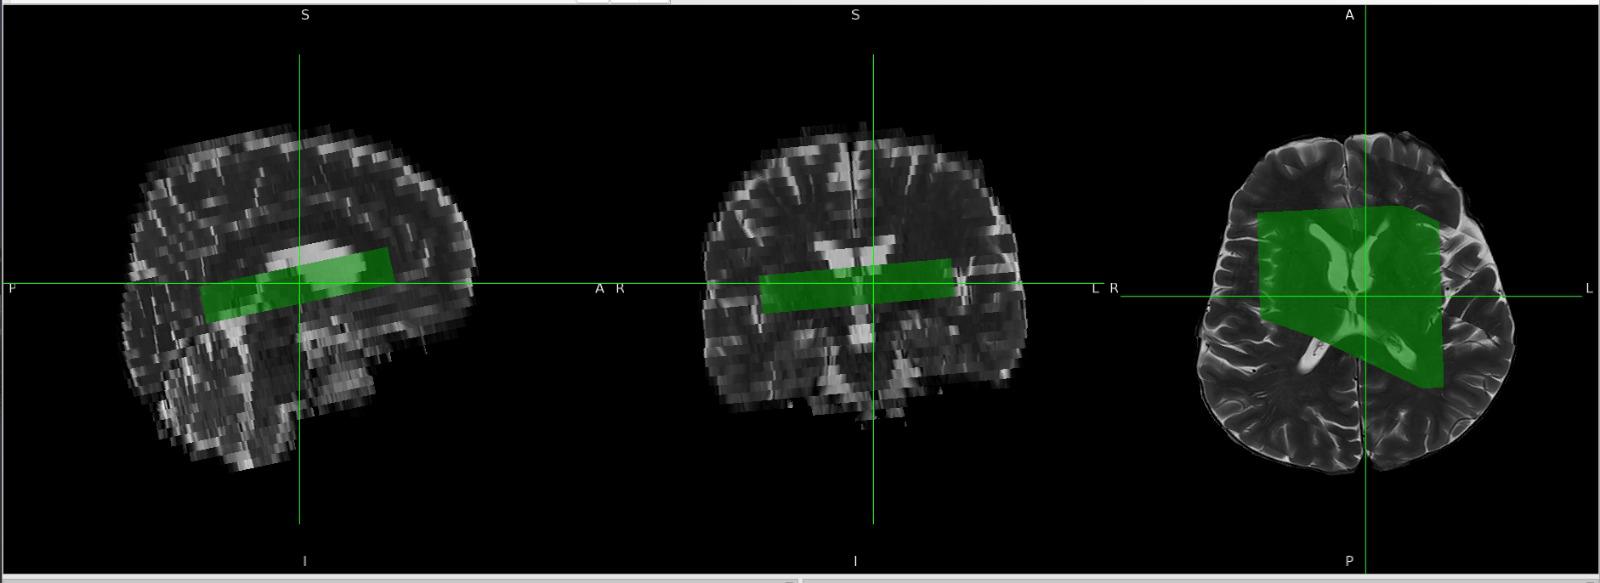

Last week, I tried several approaches to derive orientation values, and I think I have found a method to overcome this issue. Instead of using the SlabOrientation values, I derived rotation angles (in radians) from the RowVector and ColumnVector matrices by decomposing them into Euler angles. I tested this approach on multiple datasets, and so far it appears to work well.

For voxel positioning, I used the MidSlabPosition matrix instead of PositionVector. Apart from these changes, I did not make any major modifications to the existing code.